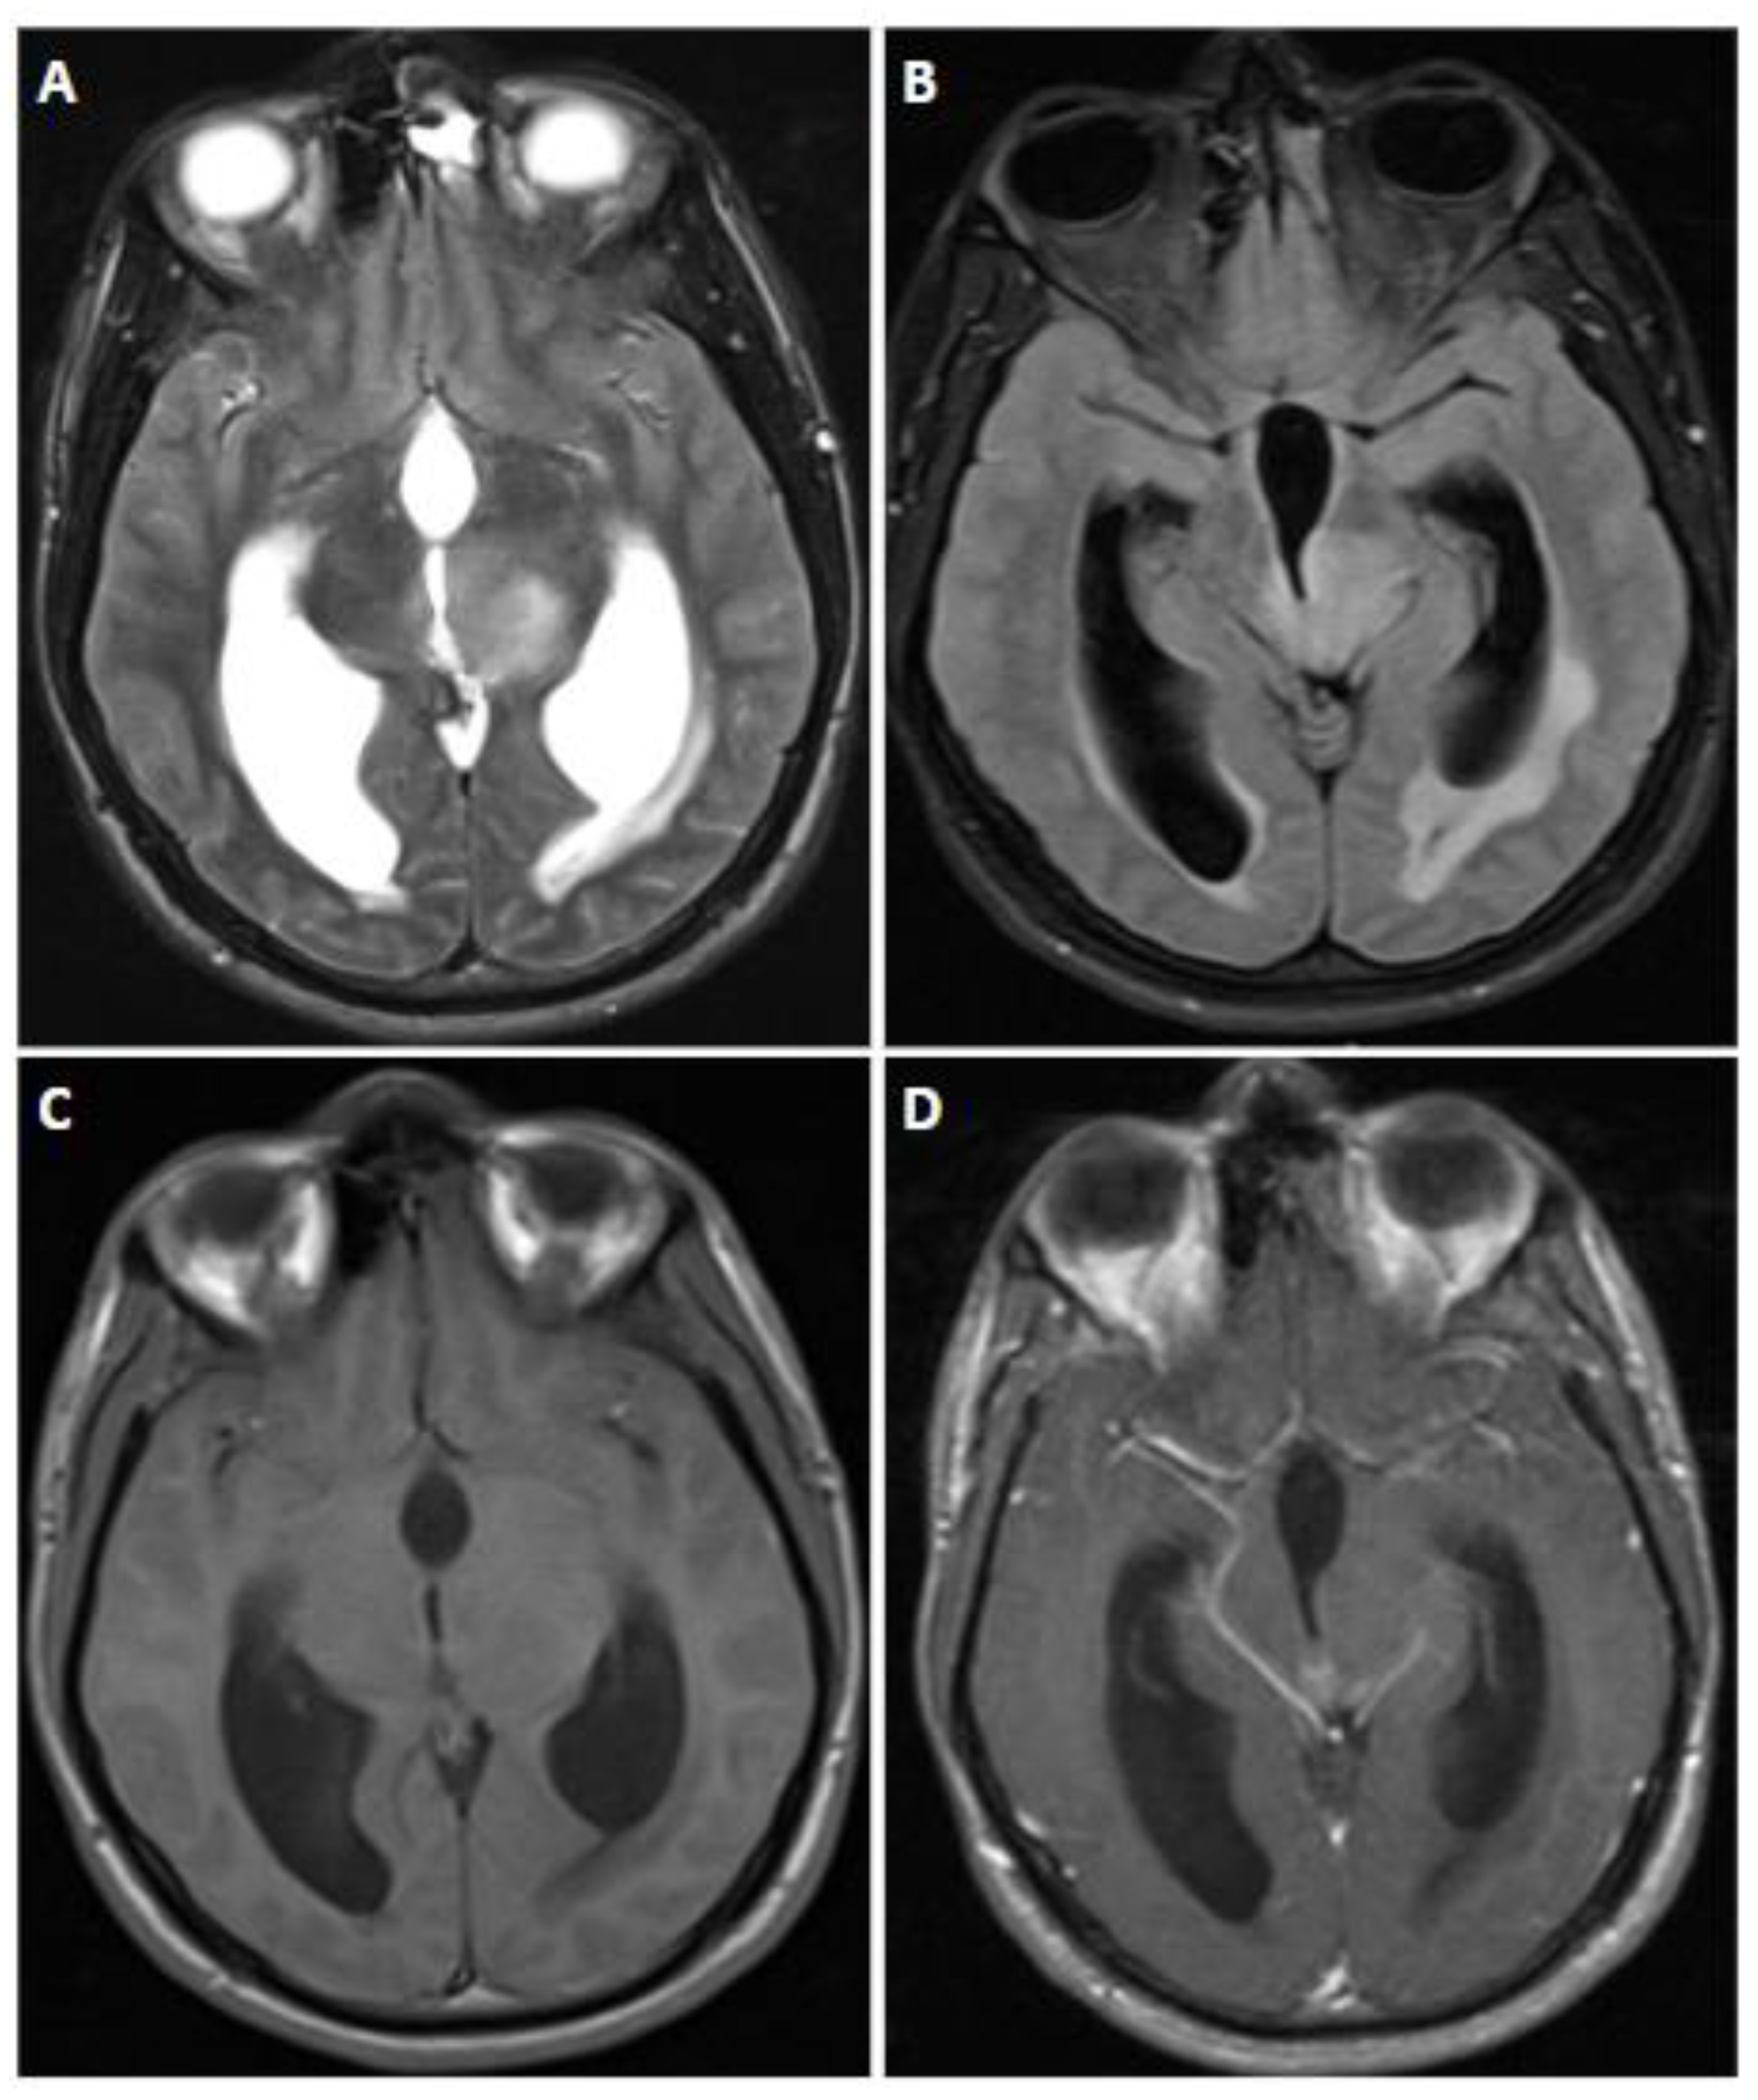

4. Oligodendrioglioma, IDH-Mutant and 1p/19q-Codeleted

4.1. Epidemiology and Localization

4.2. Brief Genetic Overview

4.3. Clinical Features

4.4. Imaging

| Oligodendroglioma, IDH-mutant and 1p/19q-codeleted | IDH1, IDH2, 1p/19q, TERT Promotor, CIC, FUBP1 | CDKN2A/B homozygous deletion indicates a CNS WHO grade 3 | Heterogeneity, calcification, variable enhancement, possible increased rCBV |